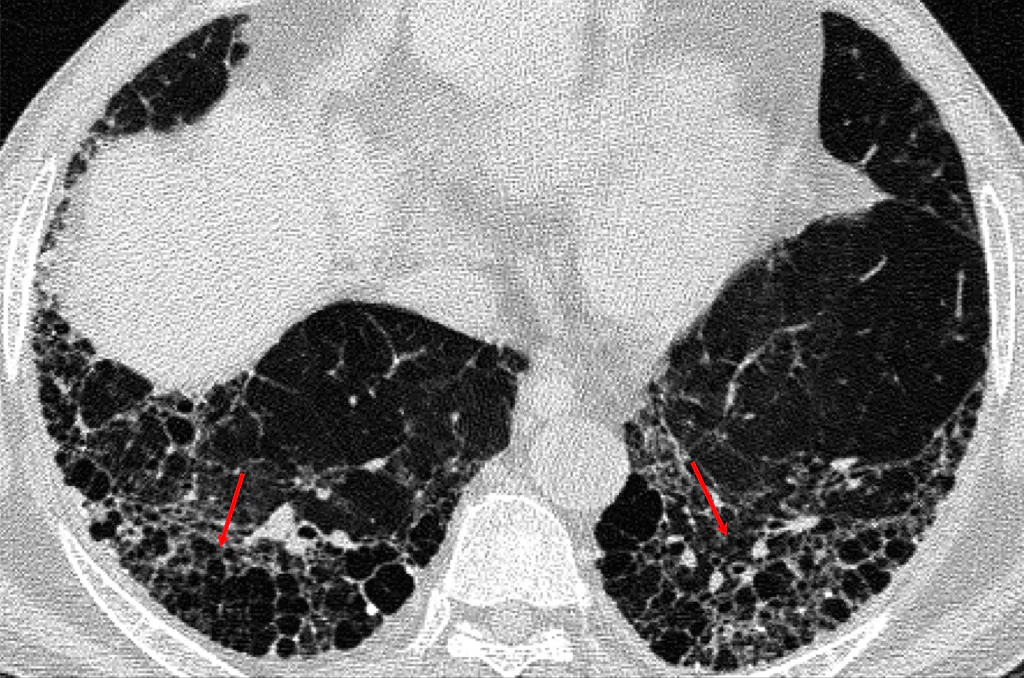

We are pioneers in the use of different CT procedures including dental CT. CT Scans of different parts of the body are obtained. Usually oral and injectable iodinated dyes have to be used.